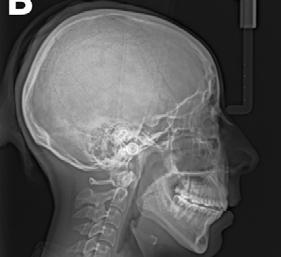

En la ortopantomografía se observó asimetría de las ramas mandibulares, reabsorción radicular severa del diente 21, extrusión de incisivos inferiores y presencia de los dientes 18, 28 y 48 (Figura 2 A). La radiografía lateral de cráneo nos permitió realizar el análisis cefalométrico de Ricketts en el cual se confirmó la clase II esqueletal, el biotipo dolicofacial y la retrusión mandibular (Figura 2 B y C y Tabla 1).

Figura 2. Radiografía ortopantomografía y lateral de cráneo.

En la ortopantomografía se puede apreciar el cierre de la mordida abierta anterior y la preservación de las longitudes radiculares en general (Figura 7A). En la radiografía lateral de cráneo y superposición final se puede observar la mejora general del perfil de la paciente y de sus inclinaciones dentales (Figura 7 B-D) (Tabla 1).

A) Ortopantomografía. B) Lateral de cráneo.

C) Trazado cefalométrico. D) Superposición.